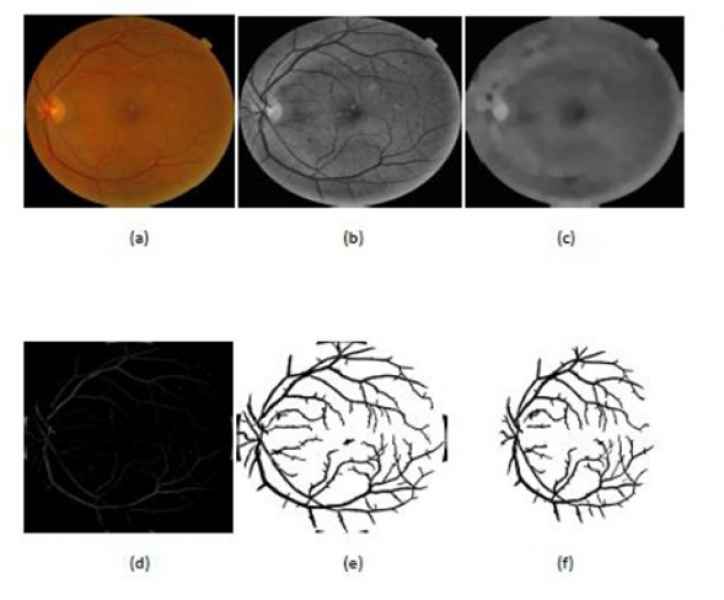

“Ahora lo que estoy trabajando es en el análisis de imágenes de fondo de ojo. Esas imágenes las clasifico en el grado de la enfermedad que tienen. La idea es hacer esto utilizando una tecnología llamada redes neuronales (subconjunto del machine learning) convolucionales, esto es para automatizar el proceso de detección”.

"Con este software que estoy haciendo, extraigo las venas, las aisló completamente del ojo y el médico puede hacer un análisis más detallado solo de las venas y también extraigo, exudados, micro aneurismas y las hemorragias en caso de existirlas". Dicho software aún se encuentra en proceso de pulimento.